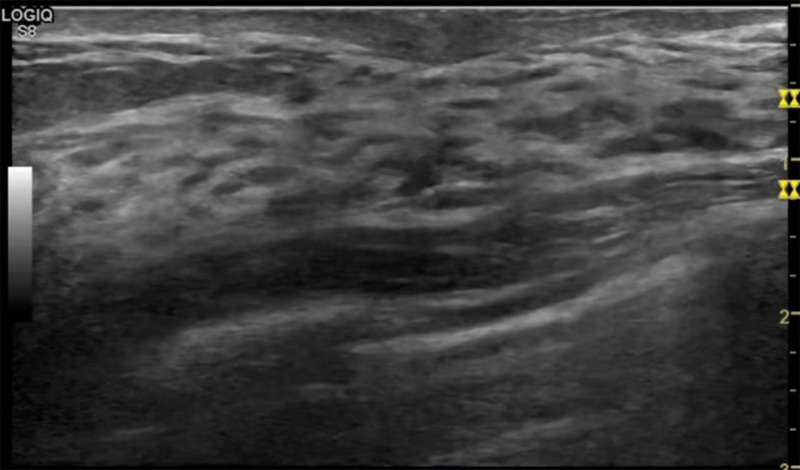

乳房脹痛,觸摸疼痛,手摸起來感覺有腫塊。這個(gè)是什么問題呢?醫(yī)生診斷一般是乳腺增生。那么在乳腺超聲設(shè)備檢查后,報(bào)告單卻顯示雙乳未見明顯占位性病變。乳腺增生是很多女性,特別是育齡期女性都有的經(jīng)歷、到底乳腺增生癥狀有哪些?會(huì)給我們帶來怎樣的影響呢?乳腺增生不是腫瘤跟炎癥。乳腺組織增生及退行性變跟內(nèi)分泌功能紊亂有關(guān)系。正常的生理改變。還有乳腺病,良性乳腺結(jié)構(gòu)不良等名稱。

乳腺增生有什么癥狀,病因?比較典型的就是乳房疼痛,特別是經(jīng)前癥狀比較重,經(jīng)后就有所緩解。有時(shí)候還能碰到乳房硬塊。根據(jù)經(jīng)期的變化而變化硬度大小都有變。乳腺在內(nèi)分泌激素,伴隨月經(jīng)周期有增生問題。內(nèi)分泌激素代謝失衡,雌激素水平增高,出現(xiàn)乳腺組織增生過度,增生組織不退的情況下,就會(huì)有乳腺增生癥狀。這個(gè)不會(huì)增加乳腺癌的風(fēng)險(xiǎn)。所以不用緊張的。不過乳腺癌的病人都會(huì)有乳腺增生。所以乳腺增長(zhǎng)有沒癥狀,都需要進(jìn)行常規(guī)的體檢。